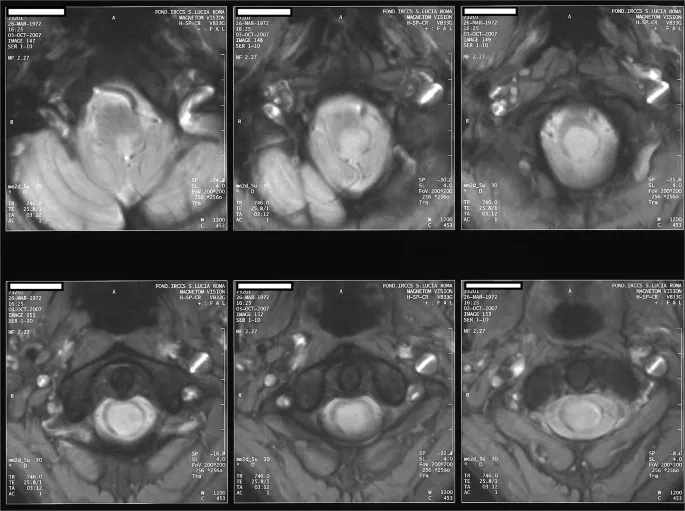

• Regular monitoring with MRI scans is essential to track the size and progression of the syrinx and determine the best timing for surgical intervention.

A before-and-after MRI following syringomyelia treatment